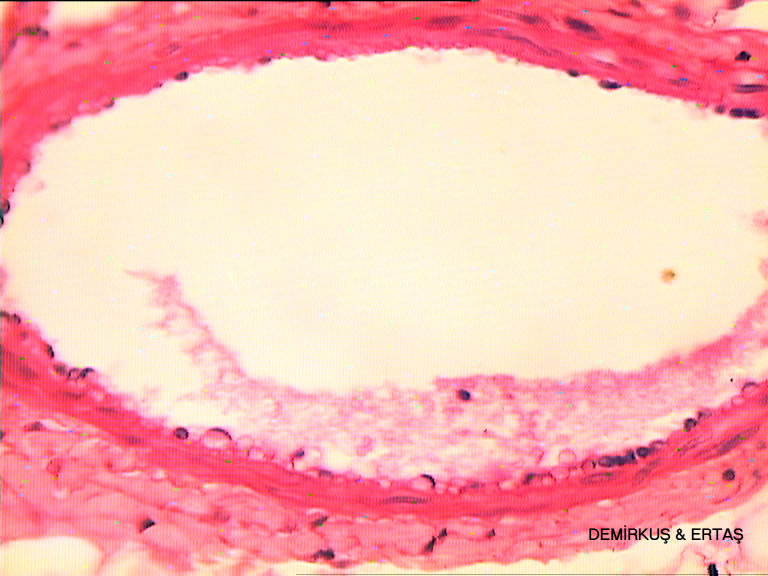

a/Atardamar-4-(Artery&vein)-.jpg